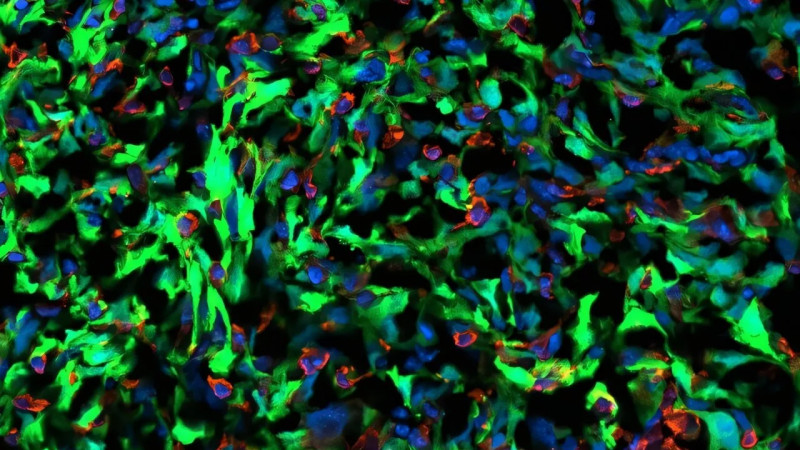

Úžasné zprávy ze světa vědy! Týmy z MIT a Harvardu objevily sloučeninu veticillin A, která účinně likviduje rakovinné buňky při testech na gliomu. Po 50 letech výzkumu máme naději na nové možnosti léčby rakoviny! #Věda #Rakovina #NovéMožnosti

Vědci dosáhli pokroku v léčbě rakoviny. Klíčem jsou houby

Vědci popsali, proč rakovina prsu metastázuje do mozku. Otevřeli cestu k léčbě